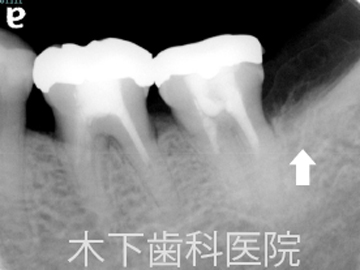

術後3年

歯周外科術後